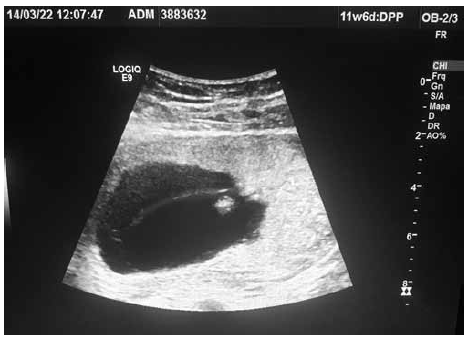

Paciente com IG de 12 semanas pela DUM veio à medicina fetal para realização de seu primeiro ultrassom obstétrico. Identificadas as figuras 1 e 2 (em ângulos e posições diferentes), conforme ilustrado.

Figura 1

Figura 2

Com base nas imagens em conjunto, assinale o diagnóstico correto é: